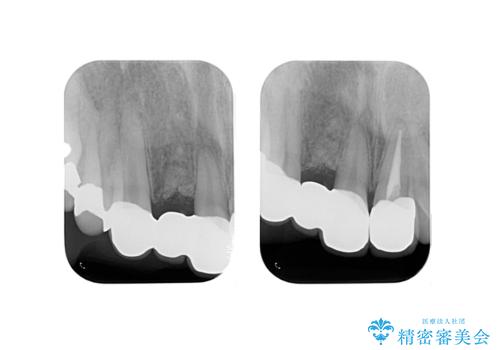

右上2番の周りの歯槽骨がかなり吸収が進んでいた影響で、抜歯後そこが大きくへこむことが予想されました。

抜歯後即時にバイオスを詰めることで抜歯後の骨の吸収をなるべく抑える治療(ソケットプリザベーション)を行いました。

歯槽骨が吸収してしまった右上1(隣の歯)との境界については右上1番遠心の歯周ポケットが深いことについては解決できない為、いずれまたダミーの歯の部分に関しては歯肉が下がってしまうことについては説明済みです。

ただ、年齢も鑑みて、直ちに右上12抜歯ではなく、まずは2番のみの抜歯でブリッジにする処置を行いました。